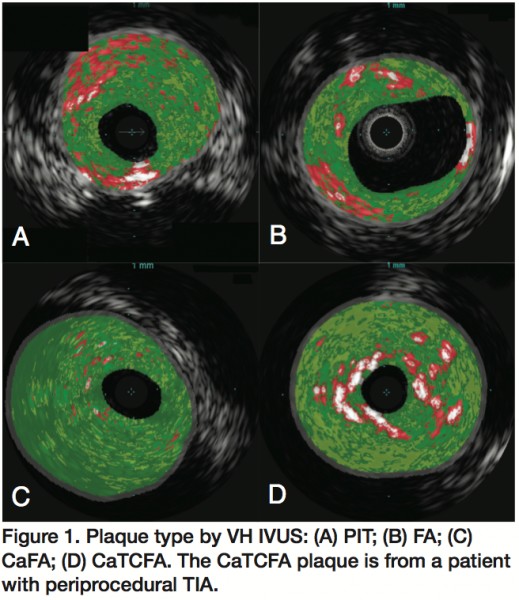

VH IVUS was performed with the 20 MHz Eagle Eye® Gold Catheter (Volcano Corporation, Rancho Cordova, California) via manual pullback (1 mm/sec) immediately after placement of the embolic protection device. Two observers (BMW and GMS), blinded to each other and to patient characteristics and periprocedural events, analyzed all segments offline (Volcano s5 version 2.2.3, Volcano Corporation). Up to 30 frames per patient were analyzed. Plaque type was classified according to Diethrich et al17 in the CAPITAL study into PIT, FA, FC, CaFA, TCFA, and CaTCFA. CAPITAL plaque definitions are as follows: PIT: intimal media thickness was >600 mm, the fibrofatty plaque component was >10%, and there was confluent NC or calcium that amounted to <10% of the total plaque cross sectional area; FA: confluent NC >10% of the total plaque cross-sectional area; FC: confluent area of calcium >10%, with NC and fibrofatty plaque each <10% of the total plaque cross-sectional area; CaFA: FA with a confluent area of calcium; TCFA: NC >10% of the total plaque cross-sectional area, and the NC was confluent against the lumen; CaTCFA: TCFA plaque with a confluent area of calcium. Plaque components, lumen and external vessel borders, and plaque type were classified based on multiple contiguous frames spanning the minimal lumen area.

Representative VH IVUS plaque types are shown in Figures 1 and 2. There was 1 major ipsilateral stroke resulting in hemiplegia occurring the day after carotid artery stenting in a patient with FA plaque by VH IVUS. This patient had prior carotid endarterectomy with sequential stenoses of the common and internal carotid artery and was symptomatic before her CAS. There were 2 ipsilateral TIAs occurring immediately postprocedure. In one case, the plaque was a CaTCFA; the lesion was greater than 90%, heavily calcified, and a concomitant stenosis with dystrophic calcification of the cavernous segment was present. The second ipsilateral TIA was in an octogenarian with FA. VH IVUS plaques for these 3 patients with periprocedural TIA/stroke are presented in Figures 1D and 3.